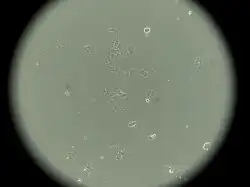

MCF-7

MCF-7 (Michigan Cancer Foundation-7) — эпителиоподобная клеточная линия, полученная из инвазивной аденокарциномы протоков молочной железы человека[1][2].

Линия была получена в 1973 году Гербертом Соулом и его сотрудниками в Институте рака Барбары Энн Карманос. До получения линии MCF-7 исследователи не могли получать линии клеток молочной железы, способной жить дольше нескольких месяцев. Сегодня эта линия является одной из наиболее распространенных линий клеток для исследований in vitro цитотоксичности противоопухолевых фармпрепаратов, молекулярной биологии рака[3], а также цитосовместимости различных биосовместимых материалов[2].